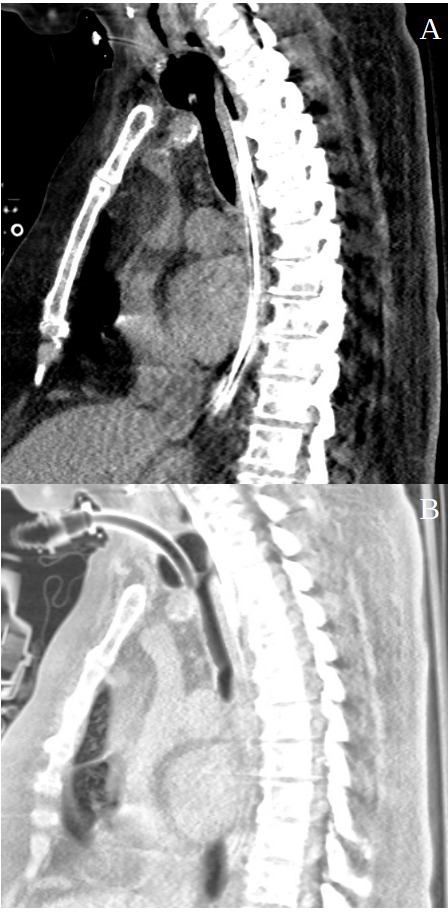

Flexible esophagoscopy initially suggested a mid-esophageal defect, but confirmation required rigid esophagoscopy with insufflation. This revealed two distinct tracheoesophageal fistulas, each approximately 4 cm in length, along the posterior-lateral tracheal wall (Figure 1).

Computed Tomography (CT) imaging performed postoperatively provided additional confirmation of tracheal cuff hyperinflation and its proximity to the fistulas. CT findings further highlighted the structural damage to the trachea and esophagus, correlating with the clinical suspicion of device-induced trauma.